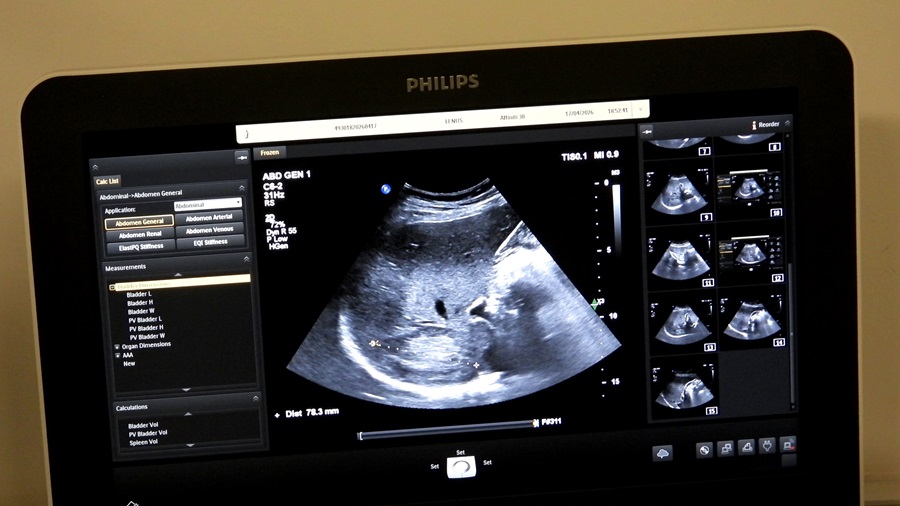

Prevencija je ključ dugotrajnog i kvalitetnog života. Redovnim pregledima možete na vrijeme otkriti promjene koje bi mogle utjecati na vaše zdravlje i osigurati pravovremenu reakciju. Ultrazvuk abdomena je jednostavna, bezbolna i sigurna metoda pregleda pomoću koje možemo pregledati organe i strukture koji se nalaze unutar trbušne šupljine. Ovaj pregled igra važnu ulogu u ranom otkrivanju promjena koje mogu dovesti do narušavanja zdravlja i razvoja bolesti.

Foto: INZ

Mnoga stanja, poput kamenaca u žuči ili bubrezima, cisti, tumora, masne jetre, ne pokazuju simptome u ranim fazama. Ultrazvuk može otkriti ove promjene na vrijeme, prije nego što dođe do simptoma bolesti. Rano otkrivanje tumora ili vaskularnih promjena značajno povećava šanse za uspješno liječenje i oporavak. Prikaz šupljih organa (želudac i crijeva) abdominalnim ultrazvukom otežan je zbog prisutnosti zraka te se za njihov prikaz koriste druge pretrage, kao što su endoskopski ultrazvuk te gastroskopija i kolonoskopija.

Ultrazvuk abdomena je posebno važan za ljude koji imaju faktore rizika, poput porodične istorije bolesti abdomena, dijabetesa, visokog krvnog pritiska ili gojaznosti. Redovni pregledi omogućavaju praćenje stanja organa i sprječavanje komplikacija. Pregled se izvodi u ležećem položaju – ljekar pregleda abdomen uz pomoć sonde na koju se nanosi ultrazvučni gel. Pregled traje od 15 do 30 minuta, bezbolan je, uređaj nema zračenja i potpuno je siguran za pacijente.